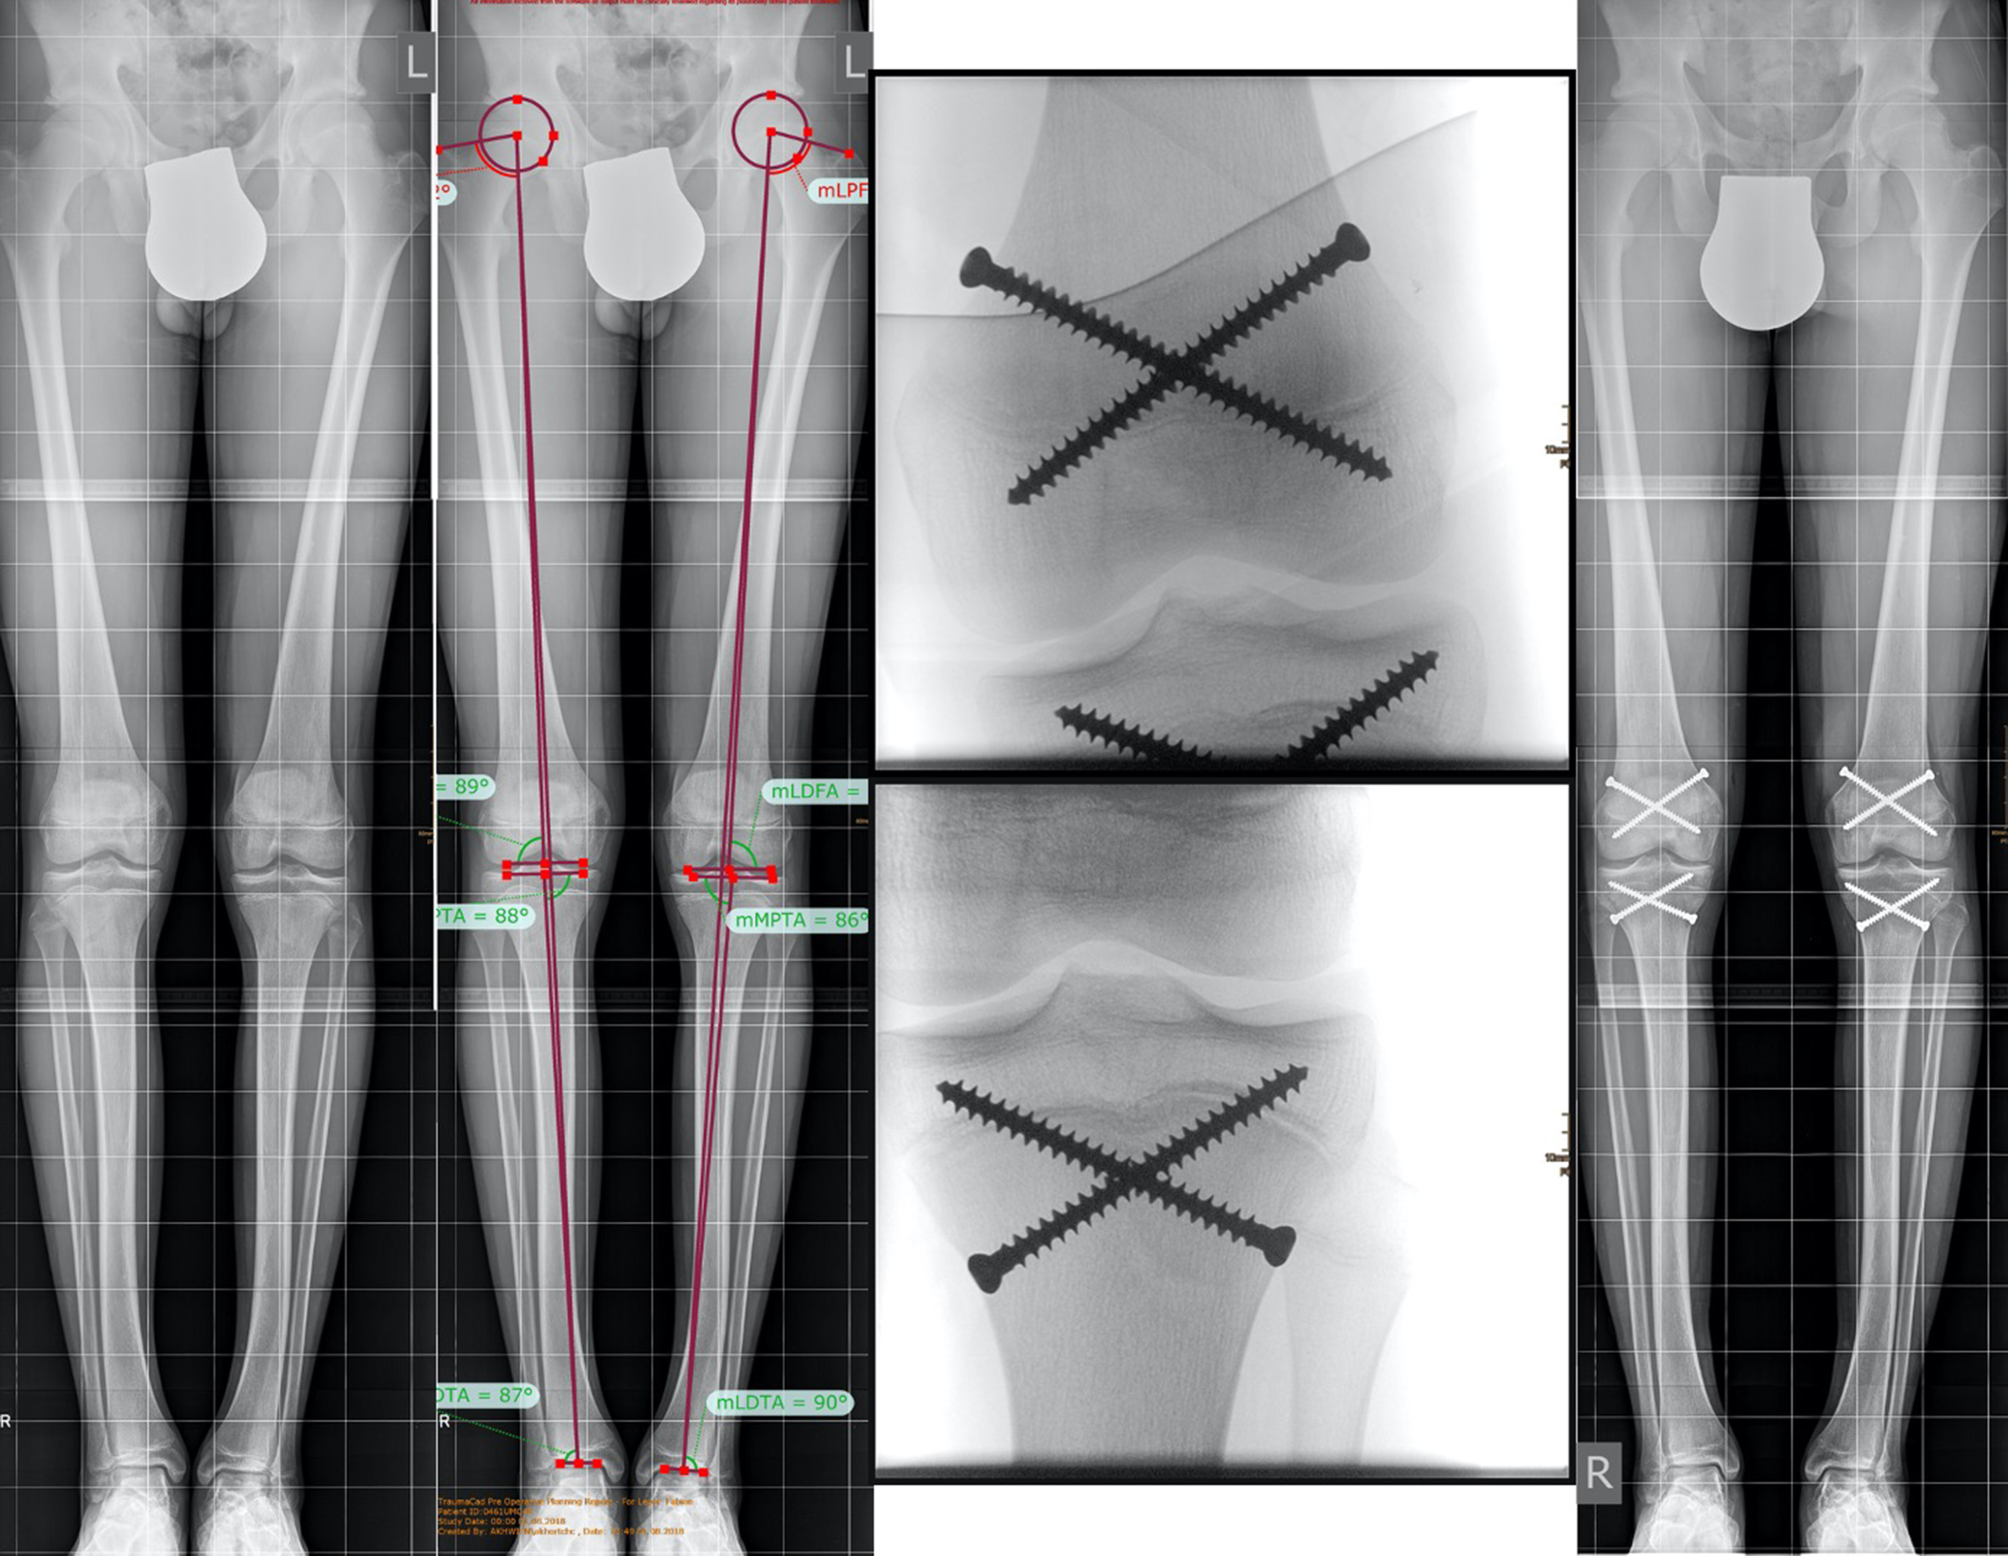

Fig. 4

Example of bilateral percutaneous epiphysiodesis using transphyseal screws (PETS) to reduce excessive predicted height. a Full standing anterior/posterior bilateral lower extremity radiograph of a boy with familial tall stature. b Preoperative limb alignment analysis. Growth prediction resulted in a predicted final height of 208 cm. c, d Intraoperative a/p x-rays of the left distal femur and tibia; e follow-up X‑ray after completed growth with a final height of 197.5 cm